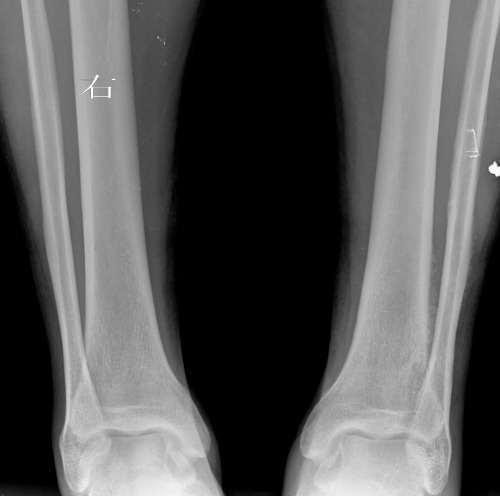

大家帮忙看下左胫骨下段外侧是骨膜反应还是骨间膜改变,或者其它病变

例1、女,48岁,以外伤就诊

双侧对比应该有